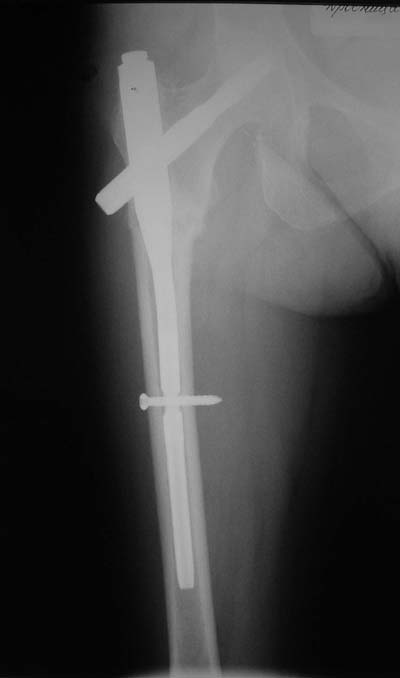

> Здравствуйте коллеги ! Прооперировали женщину 72 лет с Диагнозом: Чрезвертельный перелом

> левого бедра. Первый раз поставили PFN A (SYNTHES) см R-gr.

Дистальное блокирование провели правильно: статическое. Динамическое показано в редких случаях при поперечных подвертельных переломах.

При чрезвертельных переломах динамическая нагрузка на перелом обусловлена конструкцией клинка у PFNa, или винта у Gamma.

Присоединяюсь. Хотя посмотреть бы вторую проекцию.

И по фасу - шеечый винт можно бы и подлиннее.

Нижний винт тут, насколько я понимаю, не особо нужен, поскольку проксимальный винт проходит через дистальный отломок.

Да? Качество рентгенограмм конечно неочень, но ведь это нестабильный перелом 31.А2.2, не так ли?